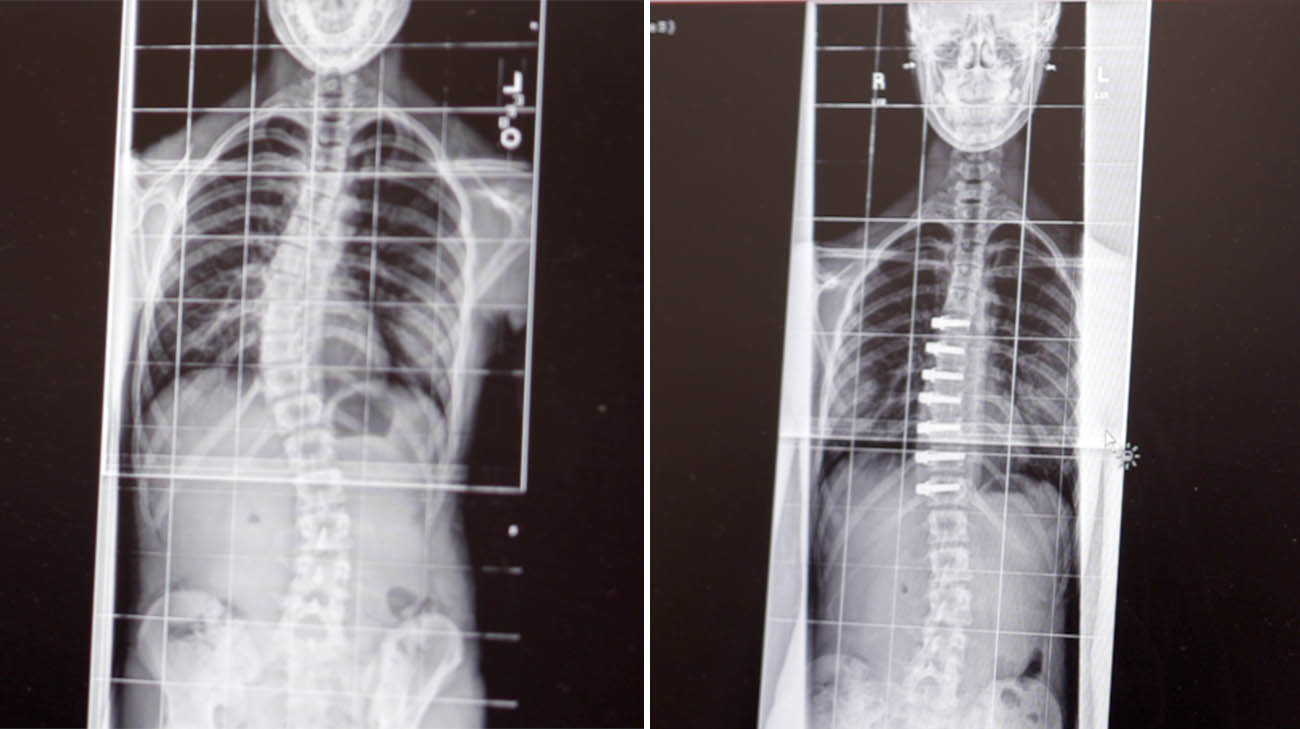

Despite wearing a corrective back brace several hours a day for four years, Aubrey’s scoliosis worsened from 22 to 28 degrees. Then, quite suddenly, as she went through a growth spurt in early 2020, her curvature increased to more than 40 degrees, a change her mother noticed while in California with Aubrey as she auditioned for a TV talent show.

Aubrey's preop scan (left) and postop (right). (Courtesy: Cleveland Clinic)